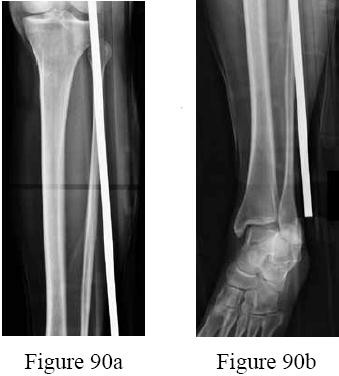

-are the radiographs of the right leg of a 30-year-old man who sustained a crush injury to his right chest, abdomen, and right leg after being pinned under a hydraulic jack. He has a blood pressure of 170/90 mm Hg. He is intubated and sedated secondary to his pulmonary injury. Six hours later he has a swollen lower leg. Examination reveals significant swelling but palpable pulses.Compartment pressures ranged from 32 to 41 mm Hg. What is the next step in management?

-is the radiograph of a 20-year-old man who kicked a door while intoxicated. At the emergency department, his leg is placed into a long-leg cast. After 2 hours, he reports increasing pain, numbness, and tingling in his toes. What is the most appropriate initial treatment?